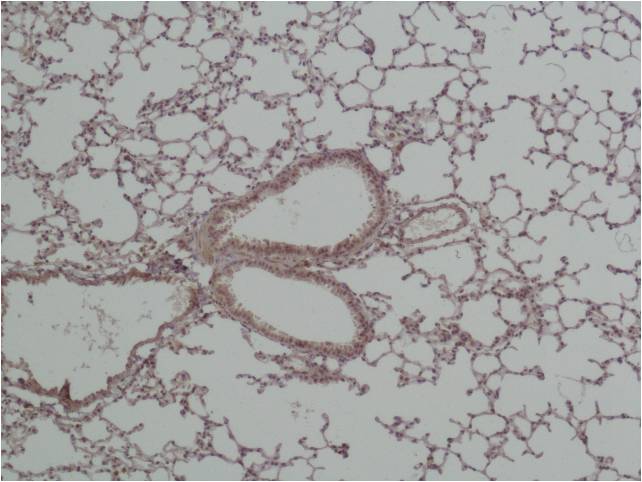

Immunohistochemical analysis of paraffin-embedded? Mouse Lung Tissue using GSK 3β(EA169)Rabbit pAb diluted at 1:500.